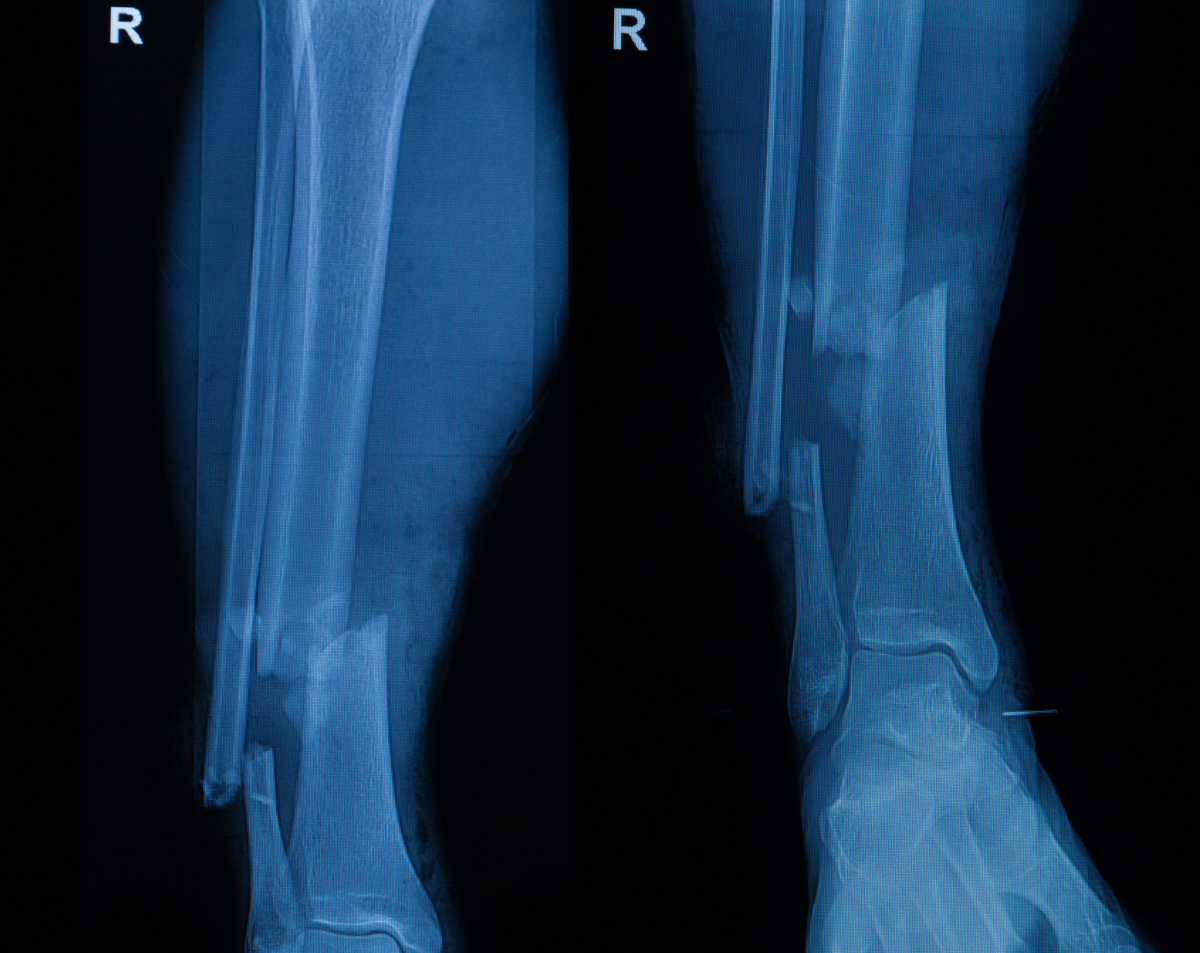

Mobile Right Tib/Fib X-Ray AH (After Hours) in Phoenix Metro

Precision Imaging for Lower Leg Pain and Injuries

A right tib/fib X-ray provides detailed images of the tibia (shinbone) and fibula (the slender bone alongside it). Physicians often order this study to evaluate fractures, infections, bone alignment, or post-surgical healing. At Desert Mobile Medical, we bring hospital-grade mobile X-ray technology directly to you—so you receive fast, accurate results without the hassle of urgent care visits or hospital delays.

When a Right Tib/Fib X-Ray AH is Needed

Injury or Trauma – To identify fractures after falls, accidents, or sports injuries.